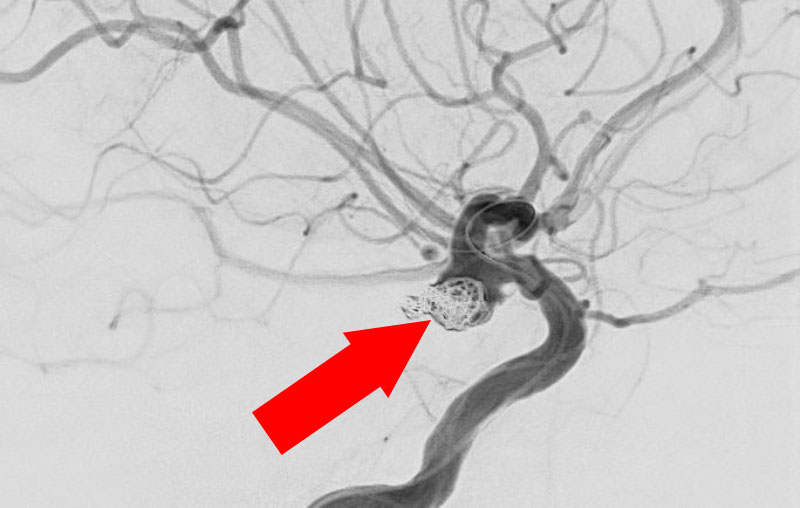

No.1185 手術前

No.1185 手術中

No.1185 手術後